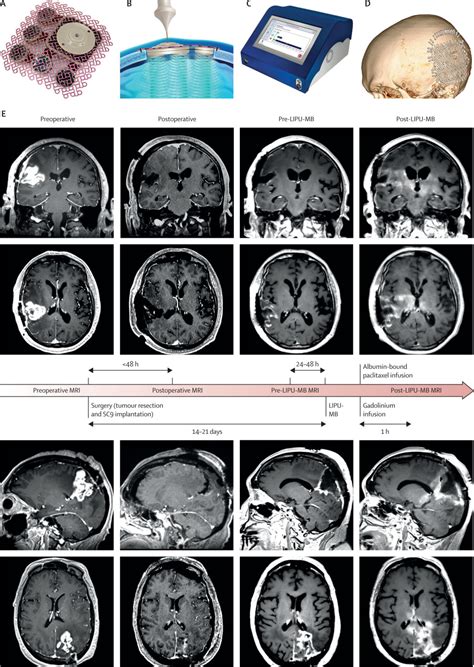

943×1327

www.thelancet.com

Repeated blood–brain barri…